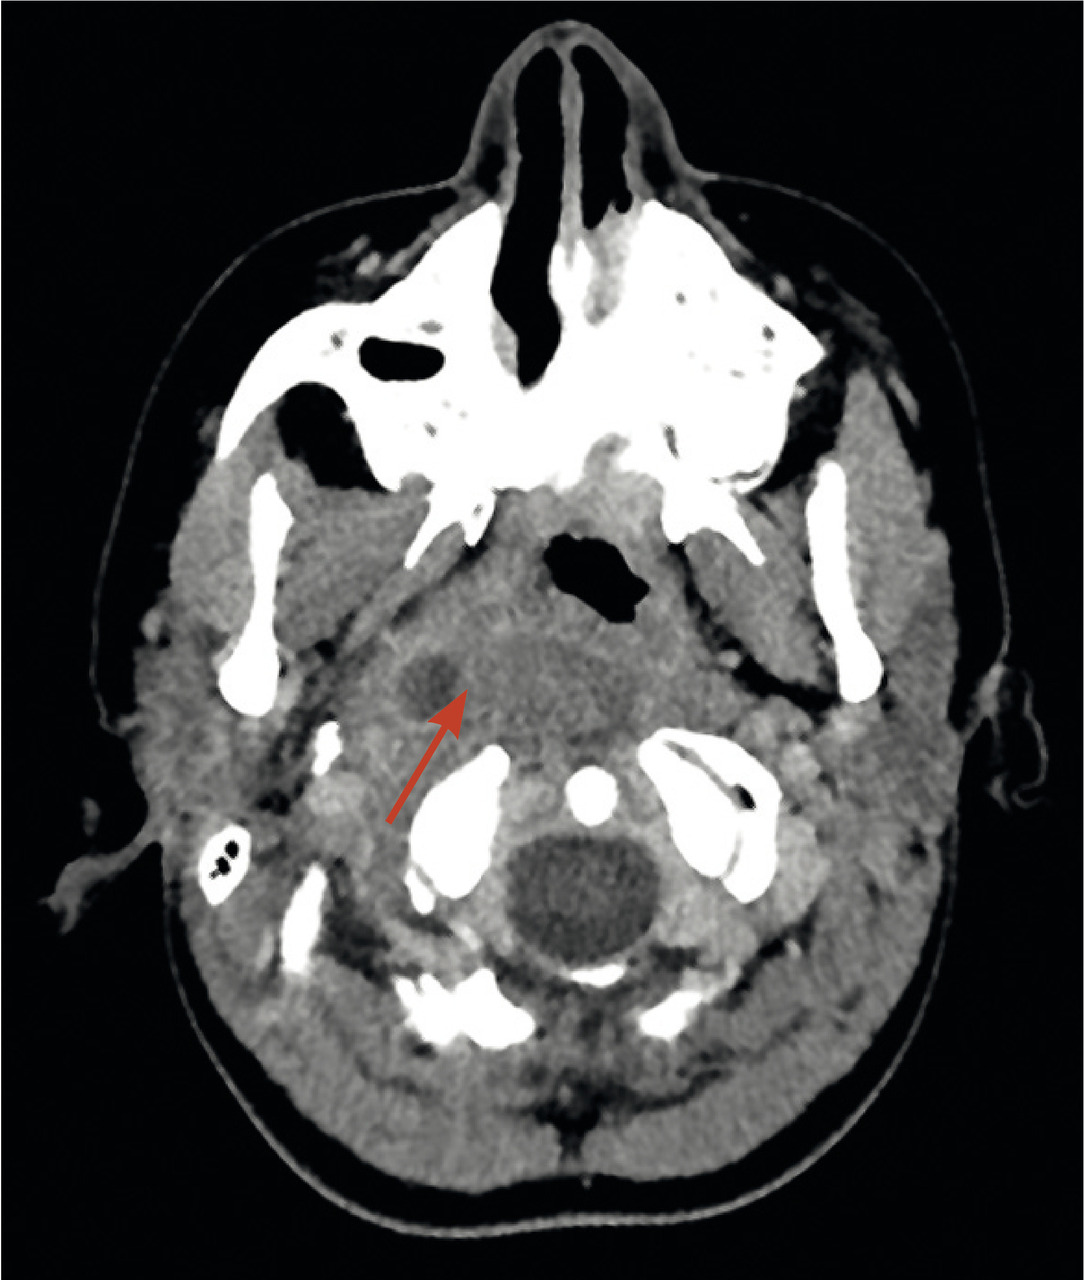

Ils compliquent les rhinopharyngites ou angines de l’enfant de moins de 7 ans. En cause : staphylocoque, streptocoque, anaérobies (comme dans le phlegmon).3 Très évocateurs : un torticolis avec hyperthermie et grande altération de l’état général. On palpe un empâtement cervical et souvent plusieurs adénomégalies. Le bombement latéral du pharynx est inconstant. Le scanner injecté confirme le diagnostic, localise la collection et d’éventuelles complications (fig. 2). L’intervention urgente consiste en une antibiothérapie IV associée ou pas au drainage chirurgical.